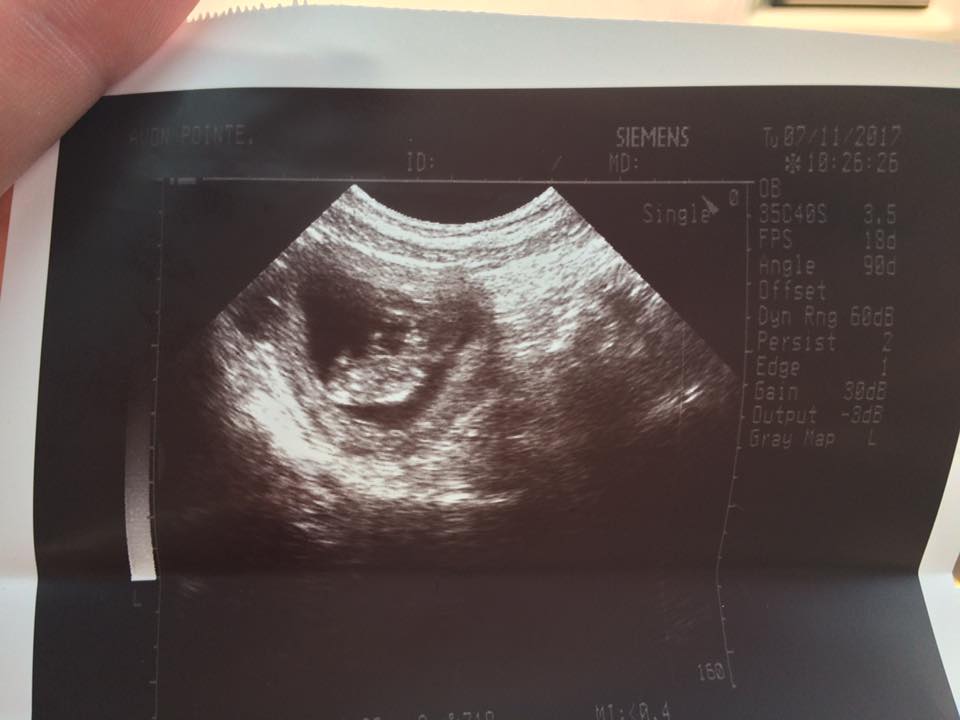

A 24 year old pregnant woman, Amber D. Horvath, of Lorain Ohio, was sentenced to serve 30 days in the Lorain County Jail today. Her sentence, which stemmed from a paraphernalia charge in January of 2017, was a misdemeanor of the 4th degree and carried a maximum penalty of up to 30 days. The young woman, who is a recovering heroin addict, also is in the midst of a 20 week high-risk pregnancy. Her high-risk pregnancy is related to the sometimes fatal disease known as endocarditis, which was caused by a staph infection that attacked her left heart ventricle a year prior.

On Monday at 1:30pm, while in open court, it was noted that Ms. Horvath had paid all of her fines, that she had been sober since March, that she had not failed a single urinalysis and that the primarily reason she couldn’t complete outpatient was a direct result of insufficient transportation. Her travel demands being great for someone without a vehicle; personal doctor appointments, pregnancy appointments, 2 AA meetings per week, 4 outpatient meetings per week, weekly probation meetings, court appearances and so on. In light of all this information, Judge Locke Graves issued the maximum sentence of 30 days to the sober, 20 week pregnant Ms. Horvath, leaving her in tears and in utter disbelief as the bailiff placed her in shackles.

Ms. Horvath also went on to state that she spends most of her days focusing on her health and trying to live a positive, productive life. That includes being around sober people and doing sober minded things. She’s also been re-united with her son and sees him frequently during many supervised visits and her next step is to regain custody of him. The photos below speak for themselves of the kind of life that she has been living since she’s beaten her heroin addiction.